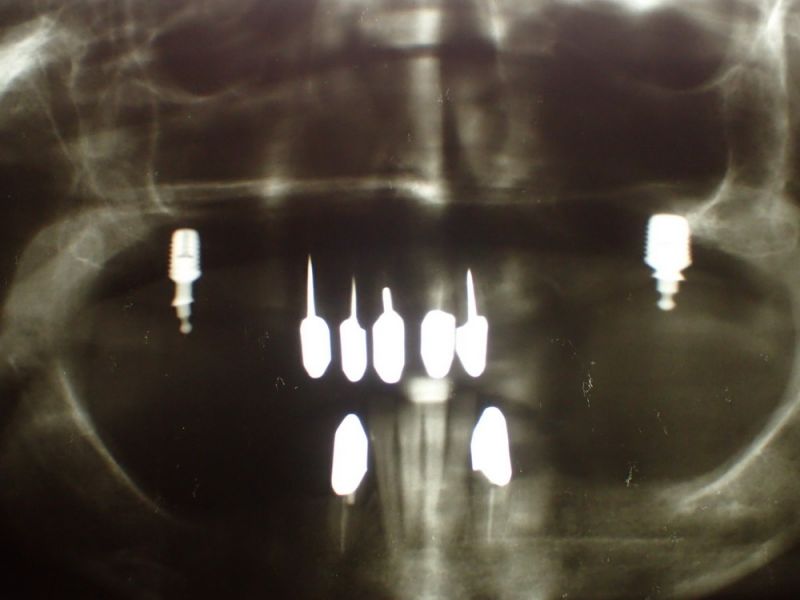

Rekonstruierte Kieler Patientin erhält ein Implantat

Nach der Entfernung des Zahnes 33 und entsprechender Abheilungsphase wurde heute ein Implantat inseriert. Nach Einheilung und Einbindung in die vorhandene Prothesenrekonstruktion soll nachfolgend dann Zahn 43 entfernt und ebenfalls durch ein Implantat ersetzt werden